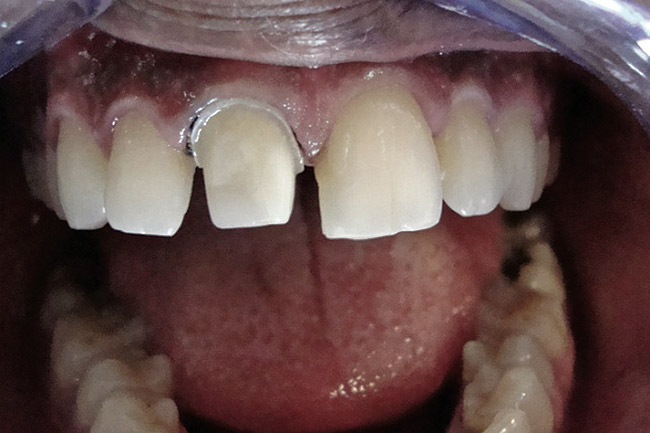

Figure 2  Caries extending cervically on upper right incisors.

Figure 2

Figure 3  Placement of rubber dam with application of cervical clamp on central incisor for extra retraction.

Figure 3

Figure 4  Final composite restorations with respect to upper right incisors.

Figure 4